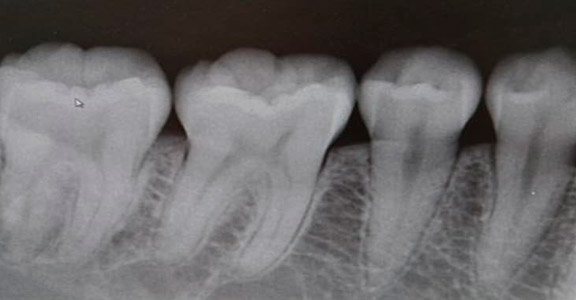

A radiografia Periapical ou RX Periapical é um exame que serve para visualizar radiograficamente a anatomia de um ou mais dentes (desde a coroa até o término da raiz), assim como as estruturas anatômicas vizinhas, ou seja, que estão ao redor dos dentes. Esta radiografia pode ser usada para estudar qualquer um dos dentes (molares, pré-molares, incisivos e caninos), seja na arcada dentária superior ou na inferior para fins de diagnóstico e tratamento.

O raio x periapical é o exame mais frequente no que diz respeito à radiografia intraoral (radiografias do interior da boca). Abrange, habitualmente, apenas uma determinada área, visualizando-se, normalmente, apenas 2 a 3 dentes contíguos (juntos), permitindo desta forma avaliar a anatomia dos dentes no seu todo de uma forma mais detalhada.